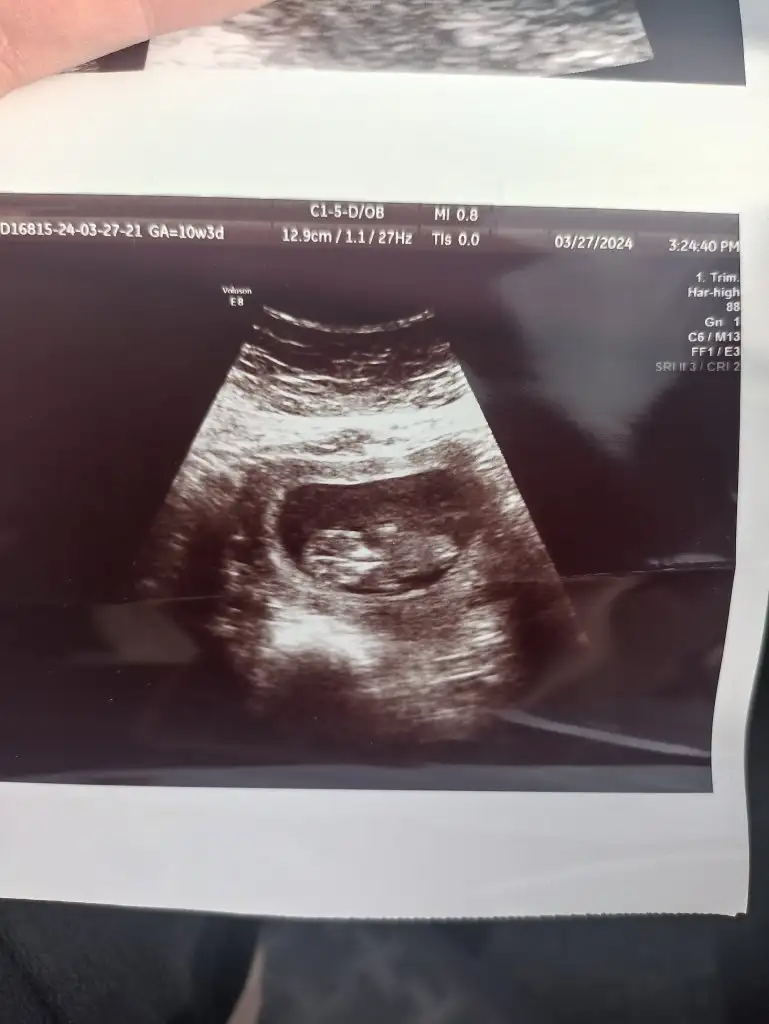

bende tahmin alabilirmiyim